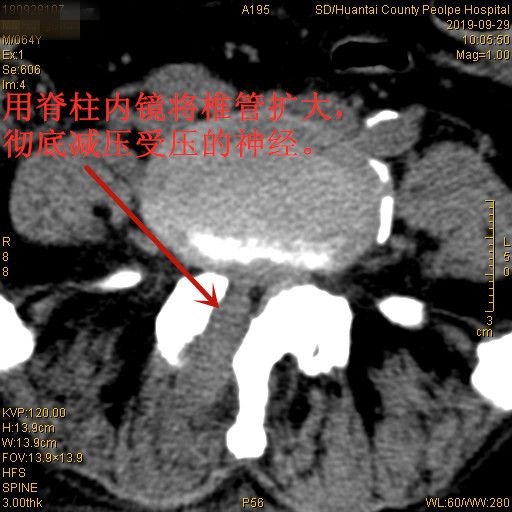

家住滨州市的马大爷,双下肢疼痛难忍,影响睡眠。老伴晚上帮他揉腿才能略有缓解,借助拐杖才能勉强行走。经过检查,马大爷的疼痛是由严重的椎管狭窄压迫神经所致。正常椎管的矢状径(既前后径)为十几毫米,他只剩下三四毫米了,加上长期卧床,马大爷右腿疼痛越来越重,到省城很多医院就诊,专家建议进行开放手术治疗,要打开椎板进行神经减压。 但马大爷患有前列腺肿瘤,他和家属都不敢尝试做大手术,于是四处打听有没有微创的办法能解决疼痛,打听到淄博市桓台县人民医院疼痛科微创水平比较高,遂来我院咨询。疼痛科汤明主任介绍,目前我院脊柱内镜技术的飞速发展,脊柱内镜能够解决所有类型的腰椎管狭窄,而且内镜治疗,创口仅0.7厘米,不剥离肌肉,恢复快,不容易留后遗症。最终患者决定在我院做微创脊椎内镜手术,手术顺利,将增生的骨质、肥厚的黄韧带全部清理干净,手术后当天就睡了个好觉,隔了一天就可以下地活动了,疼痛也都消失了。